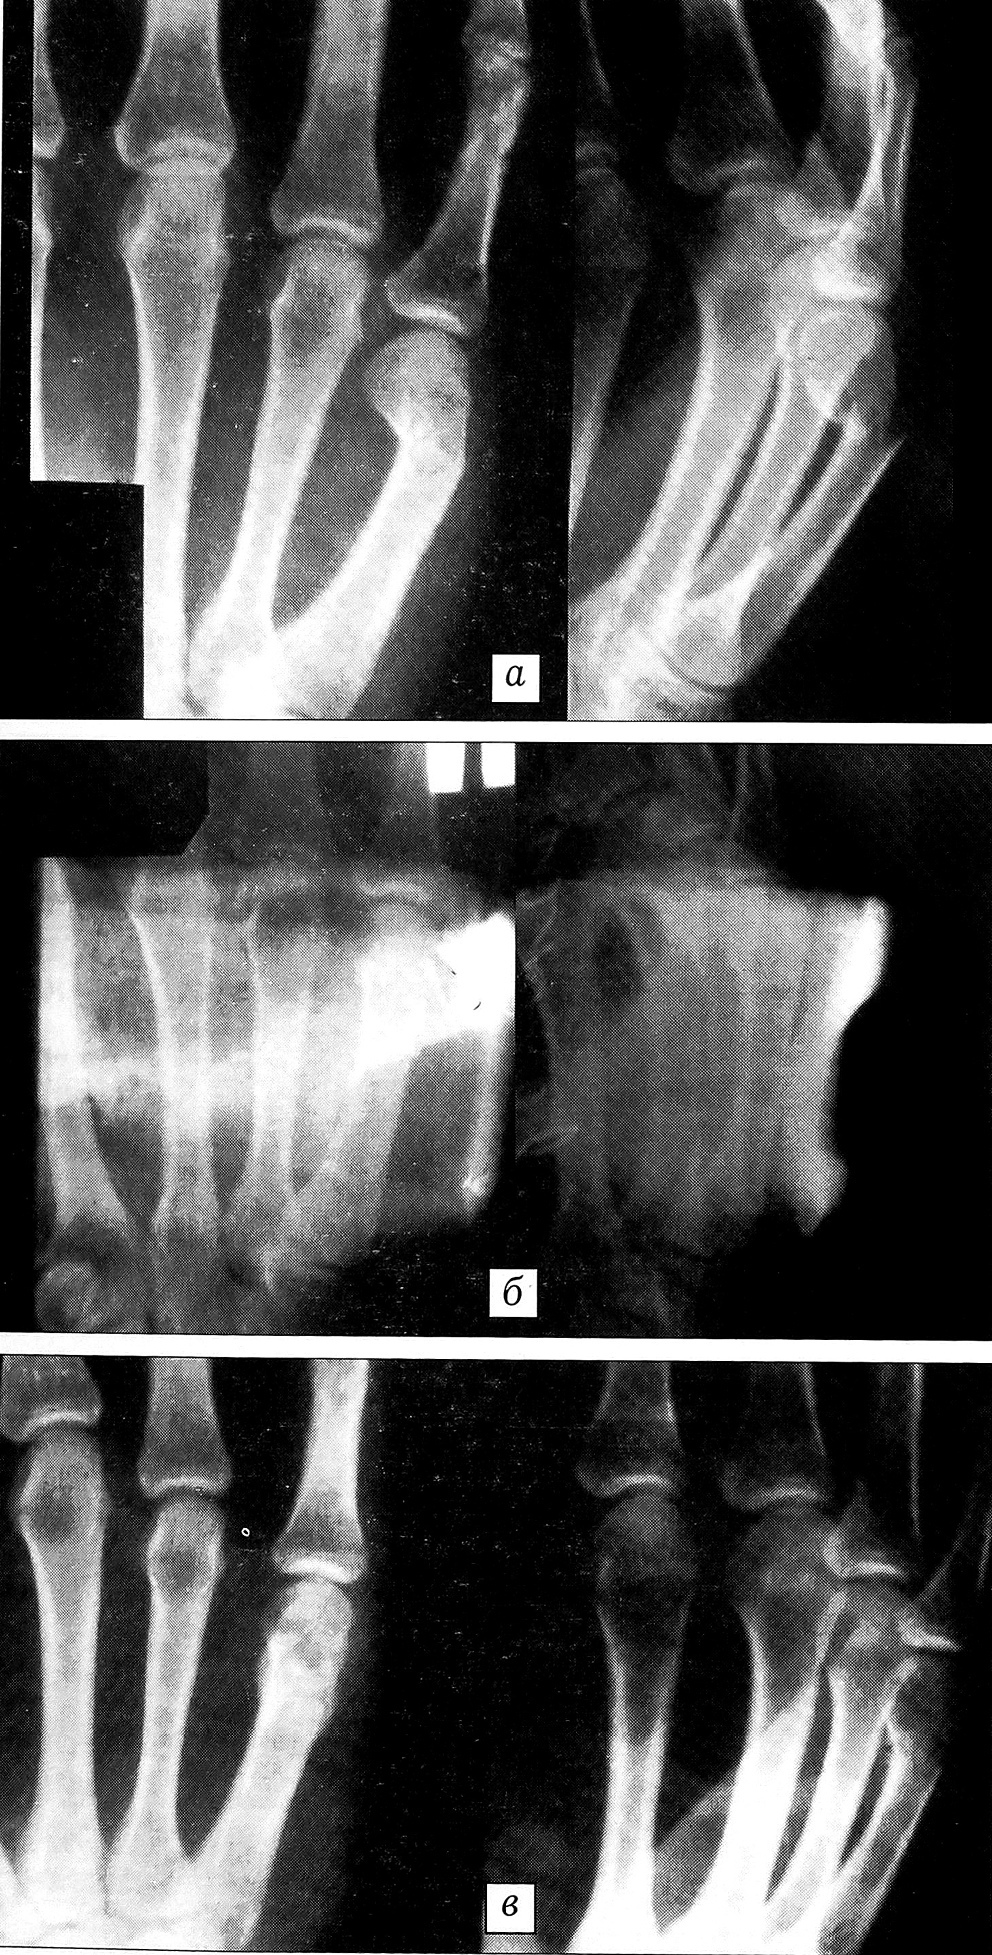

Рентгенограммы больного Р. Диагноз: закрытый перелом шейки V пястной кости правой кисти со смещением отломков.

a — при поступлении; б — после репозиции и наложения гипсовой повязки; в — результат лечения через 4 нед.

Больной Р.,31 года. Диагноз: закрытый перелом шейки V пястной кости правой кисти со смещением отломков. Травму получил при ударе во время драки. На рентгенограмме при поступлении (см. рисунок, а): косопоперечный перелом шейки V пястной кости со смещением по ширине и под углом, открытым к ладони. Через 4 ч после травмы под местной анестезией выполнена закрытая репозиция, наложена короткая гипсовая повязка. На контрольной рентгенограмме (б): смещение устранено. Гипсовая повязка снята через 4 нед, на рентгенограмме без гипса (в): положение отломков правильное. Больной осмотрен через 2 мес после травмы: сгибание и разгибание в пястно-фаланговом суставе в полном объеме, деформации пястья нет.